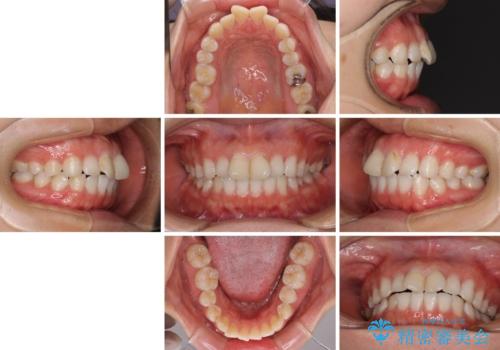

前歯の捻れを改善 インビザラインによる矯正治療

- 前歯の翼状捻転を気にして来院された患者様です。

全体的に叢生は軽度であったため、インビザラインにて矯正治療を行うこととしました。

前歯の幅の大きさも気になっていたため、IPRにより叢生を解消するとともに、歯の大きさも改善しました。